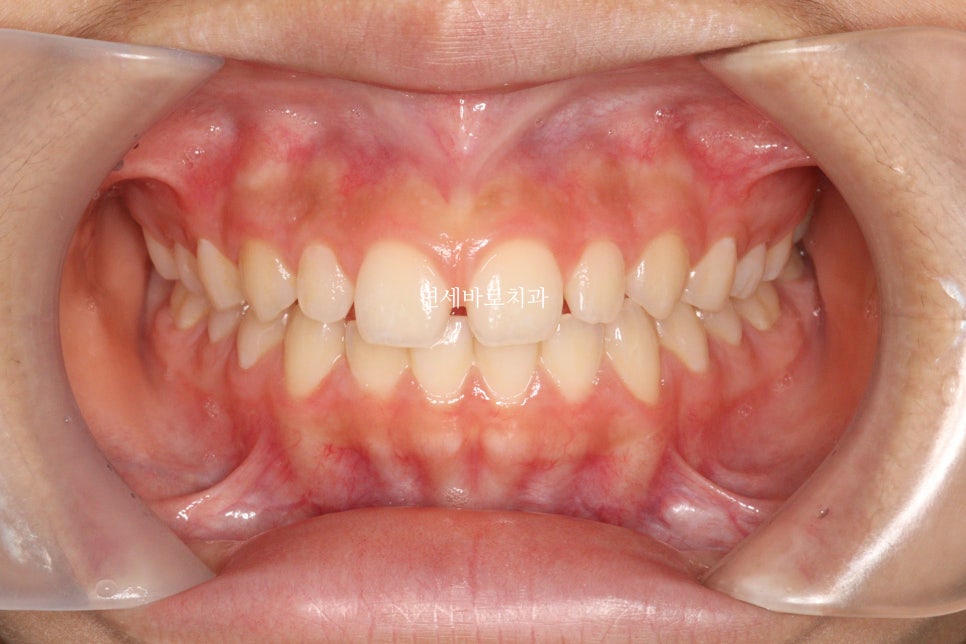

치료가 끝난 당시 모습입니다.

앞니가 듬성듬성 벌어진것이 보기 아쉽네요

이렇게 된 이유는 두가지

왜소치

앞니 형태가 항아리모양 (네모가 아님)

최종적으로 아이는 레진으로 임시로 공간을 매꾸기로 했습니다.